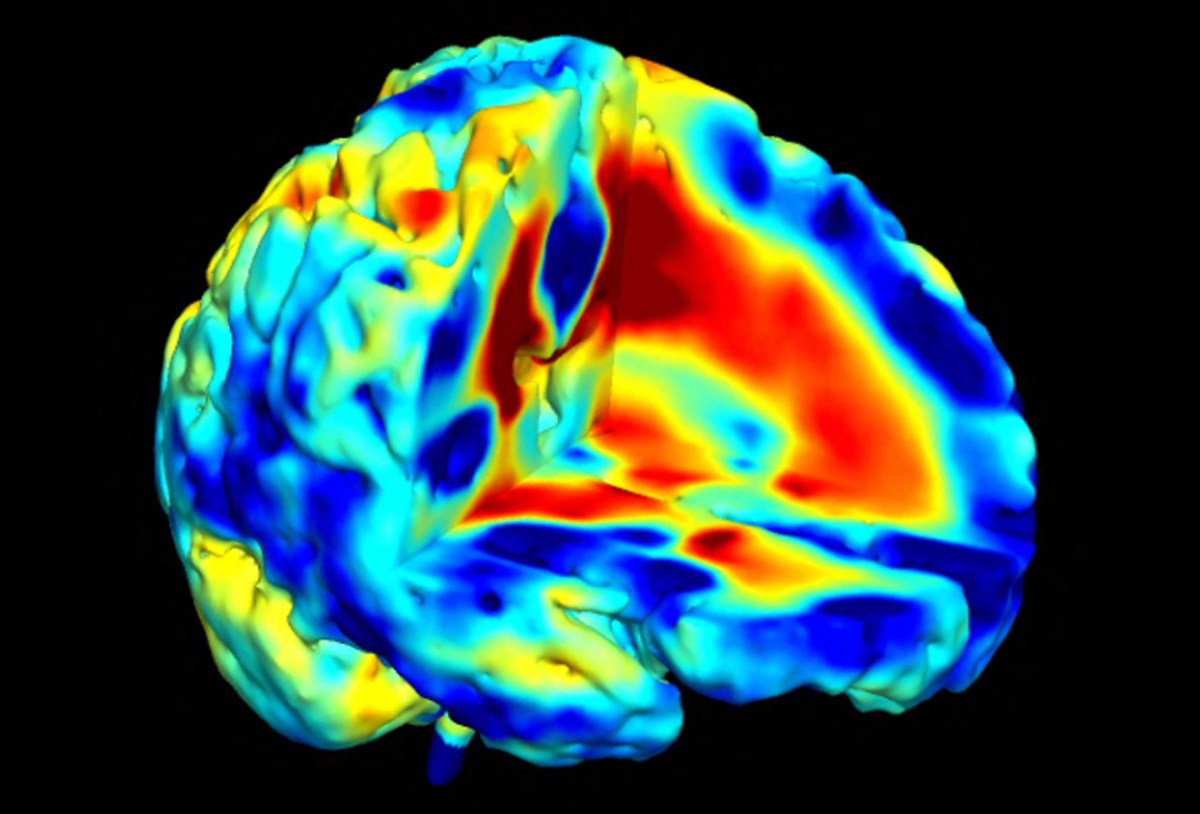

A scan showing areas of brain growth and loss of tissue for a patient with childhood-onset schizophrenia.

AFP